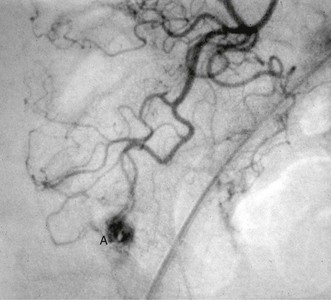

Management is rarely surgical but an angiogram and embolisation is sometimes performed by a specialist radiologist if the bleeding is severe. After necessary resuscitation, the patient is kept under observation for several days, after which it is safe to perform further investigations.

Colonic angiodysplasias have been recognised as a common cause of acute or chronic rectal bleeding and iron deficiency anaemia since the mid-1970s. The lesions are tiny hamartomatous vascular lesions in the colonic wall, usually in the ascending colon, and produce bleeding out of proportion to their size (see Fig. 29.8). They may also occur in the stomach and small bowel. The origin of colonic angiodysplasias is unknown but since they occur later in life, they are probably acquired and degenerative.

If bleeding is acute and is occurring rapidly, selective mesenteric arteriography may demonstrate the source of bleeding. In chronic or recurrent haemorrhage, large bowel lesions can be visualised by colonoscopy. This underlines the importance of thorough colonoscopy in patients with unexplained GI blood loss. Lesions can often be treated by electrical coagulation via a colonoscope. If unsuccessful, the affected segment is excised. Similar lesions occur more rarely in small bowel and bleed in the same way.